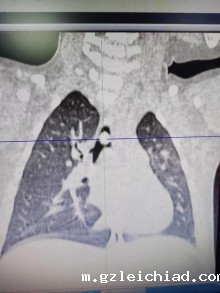

经过仔细检查后确诊为支气管内异物。在儿童重症监护室主任宋俊主导下,李瑞华医生紧急完善术前准备,与内镜中心、麻醉医生完善术前谈话和术前准备。

经过宋俊、李瑞华及麻醉医生、内镜中心护士共同的细心操作下,一颗15mm*10mm的西瓜子在镜子下成功取出,医护人员跟家属悬着的心终于归位。